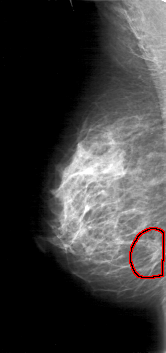

D_4030_1.RIGHT_CC

RIGHT_CC LINES 5206 PIXELS_PER_LINE 2566 BITS_PER_PIXEL 12 RESOLUTION 43.5 OVERLAY

FILE: D_4030_1.RIGHT_CC.OVERLAY

TOTAL_ABNORMALITIES 1

ABNORMALITY 1

LESION_TYPE MASS SHAPE IRREGULAR MARGINS SPICULATED

ASSESSMENT 5

SUBTLETY 5

PATHOLOGY BENIGN

TOTAL_OUTLINES 1

BOUNDARY